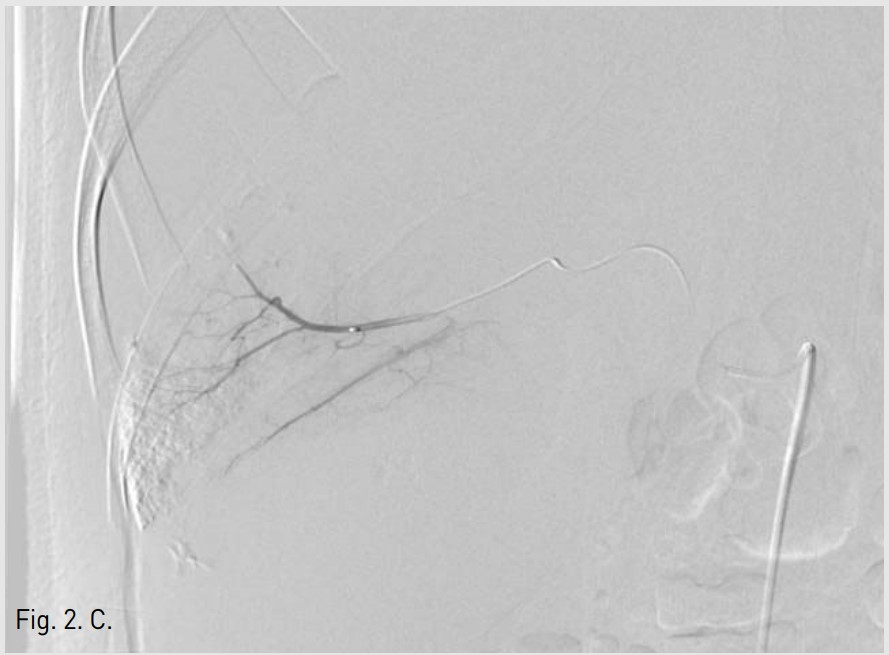

5F RH catheter (Cook, Bloomington, USA)를 이용하여 바로 시행한 간동맥조영술에서 right posterior inferior hepatic branch에서 급성출혈이 관찰되었다(Fig. 1B). 2.9F coaxial microcatheter(Stride, ASAHI, Aichi, Japan) 로 출혈혈관부위를 초선택한 후 gelatin sponge(Cutanplast, Mascia Brunelli , Milan, Italy)을 이용하여 색전술을 시행하였다(Fig. 1C). 시술 다음날 혈색소 수치는 10.0g/dL로 증가하였다. 그러나 시술 2일 후 환자의 활력징후는 혈압 131/80mmHg, 맥박수 82/min로 안정적이었지만, 혈색소가 7.8g/dL로 급격히 감소하였고, 우상복부에 심한 통증을 호소하여 재출혈의 의심하에 복부 CT검사를 시행하였다. CT검사에서 간에 다량의 피막하 혈종이 관찰되었지만, 조영제의 혈관외 유출은 보이지 않았다(AAST grade Ⅲ)(Fig. 2A). 같은 날 시행한 간동맥 혈관조영술에서 기존 색전술을 시행한 동맥에서의 재관류는 없었지만, 새로 생긴 다른 부위의 피막하혈종 내로 광범위한 다발성 미세출혈이 관찰되었다(Fig. 2B). Microcatheter를 이용하여 각 출혈부위 근처의 segmental artery들을 선택한 후 gelatin sponge를 이용하여 광범위한 부위에 색전술을 시행하였고, 더 이상의 출혈은 관찰되지 않았다(Fig. 2C, D). 시술 후 환자의 혈색소는 정상화되었고 우상복부 통증은 점차 감소하였다. 이 후 뚜렷한 합병증 없이 입원 1달 후 퇴원하였다.

Fig. 2. C

Fig. 2C. After selective catheterization of multiple bleeding arteries with a microcatheter, embolization was performed by using gelatin sponge.

Fig. 2. D

Fig. 2D. Post-embolization angiogram shows no evidence of arterial bleeding.